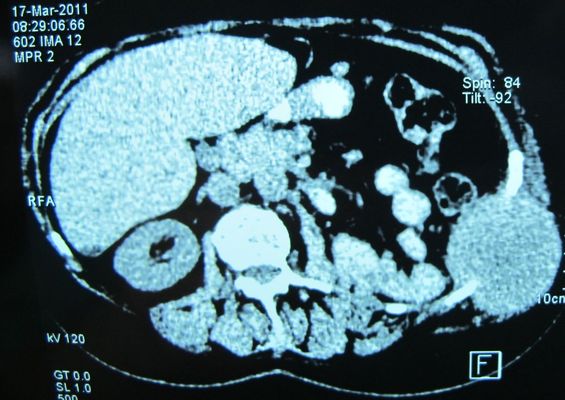

Удаление рецидива рака левой почки в брюшную стенку

Оперируют Костюк И.П. и профессор Кукушкин А.В.

Резекция 11 и 12 ребер, инфильтрируемых опухолью.